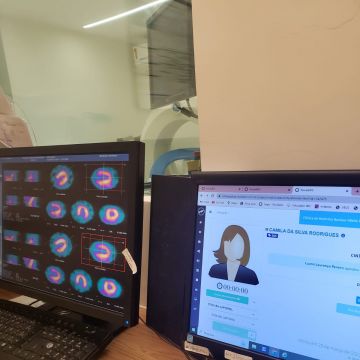

me chamo felipe, tenho 31 anos, trabalho na trabalho na área da saúde como cuidador no brasil, sou técnico de raio x e estudante de biomedicina no brasil